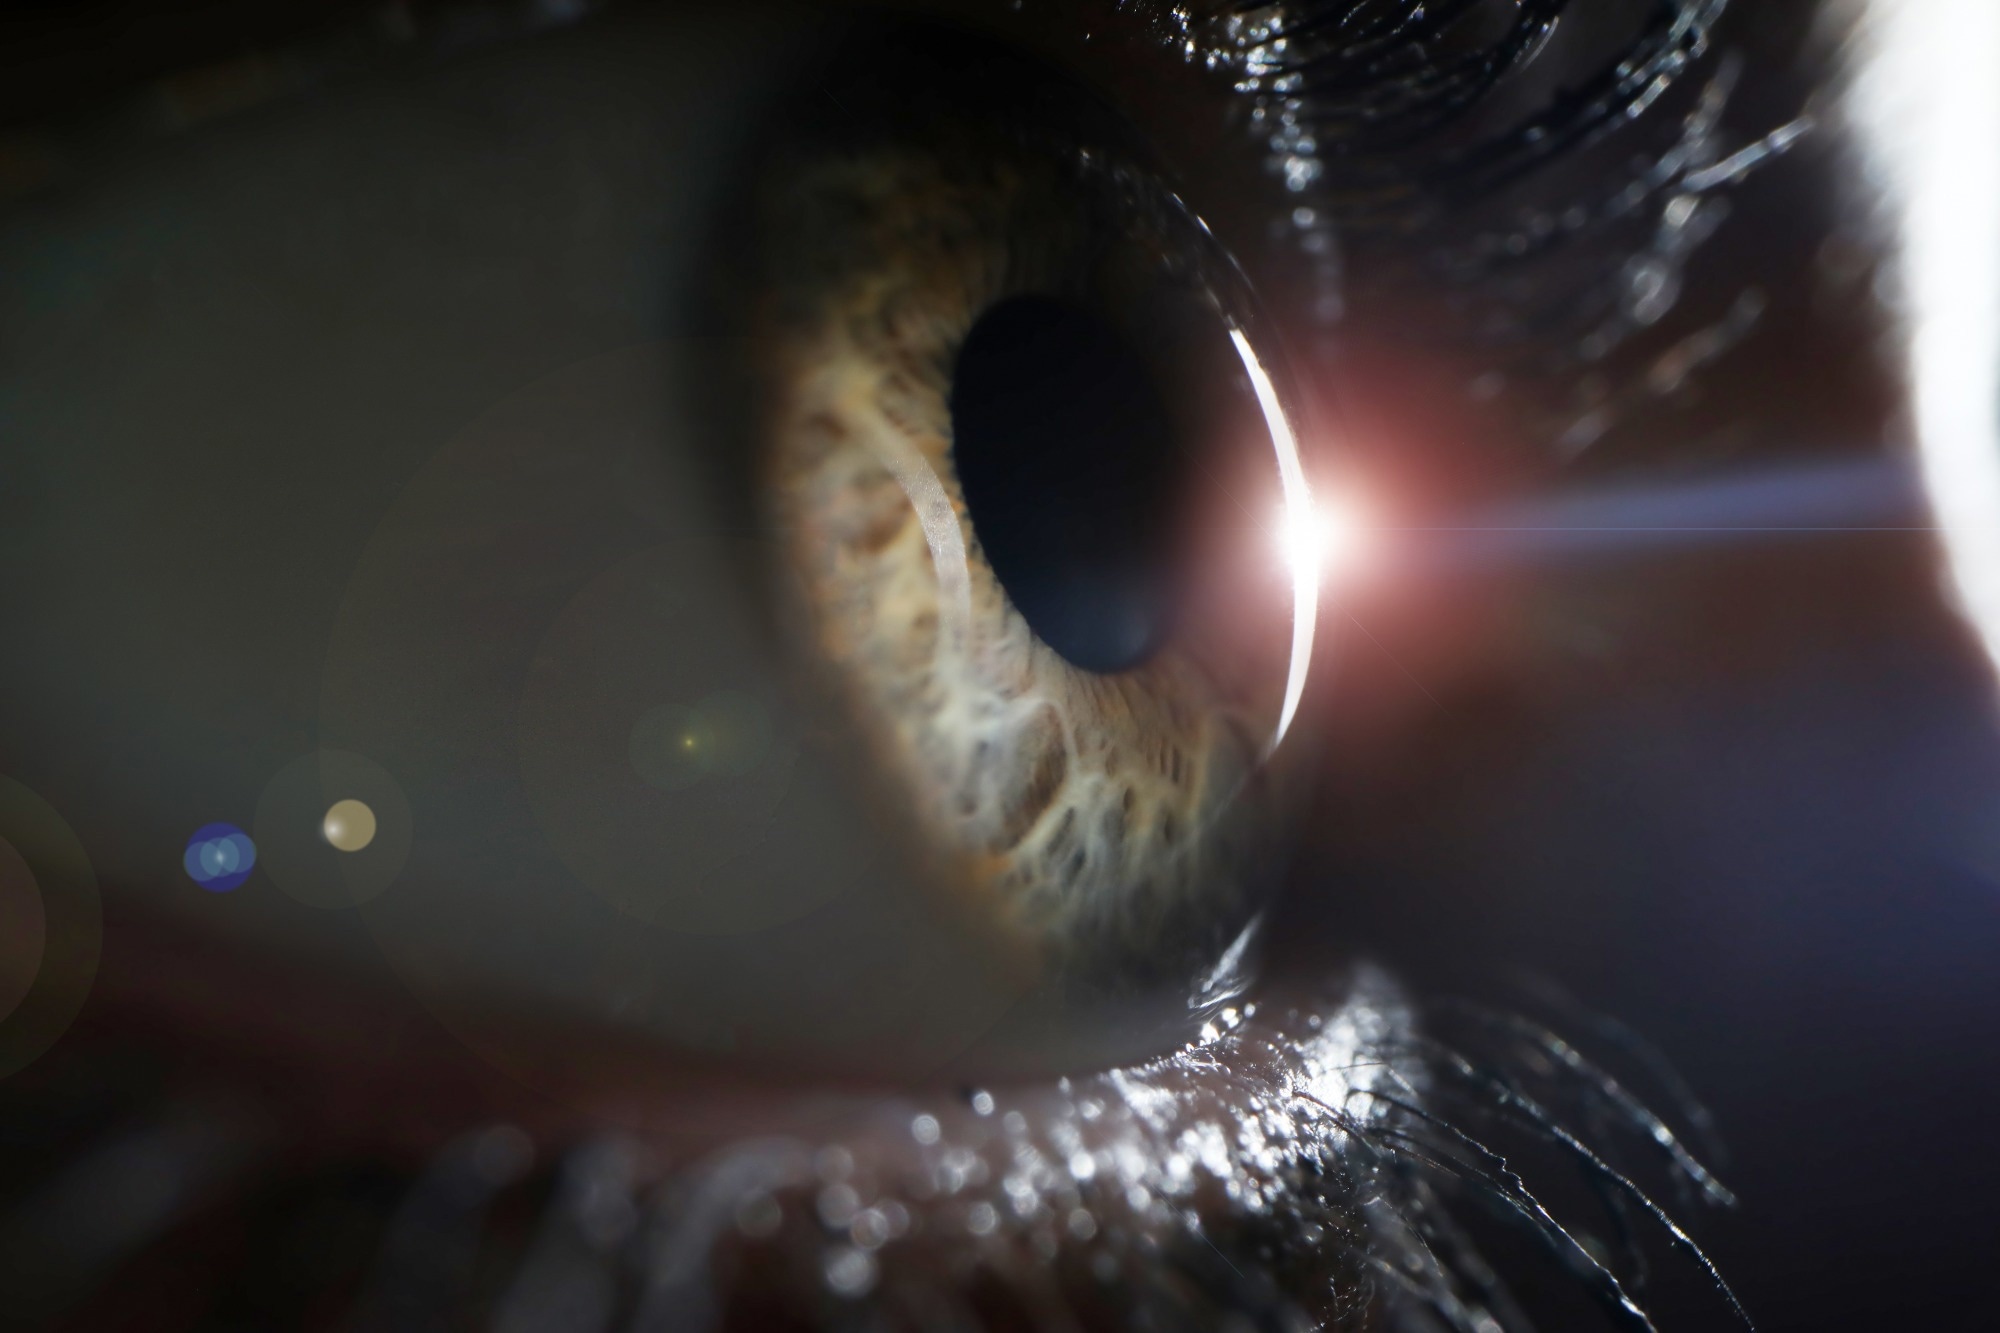

Study: Accurate estimation of biological age and its application in disease prediction using a multimodal image Transformer system. Image Credit: H_Ko / ShutterstockStudy: Accurate estimation of biological age and its application in disease prediction using a multimodal image Transformer system. Image Credit: H_Ko / Shutterstock

In the present study, the researchers developed an AI-based modeling system that uses tongue, retinal fundus, and facial images to estimate biological age and obtain information on and predict the risk of chronic, organ-specific diseases. The optic nerve contains axons derived from the central nervous system, which makes retinal images a potential indicator of brain health. Furthermore, microbiome exposure deduced from tongue images can be an indicator of the health of the oral cavity and the gastrointestinal tract.